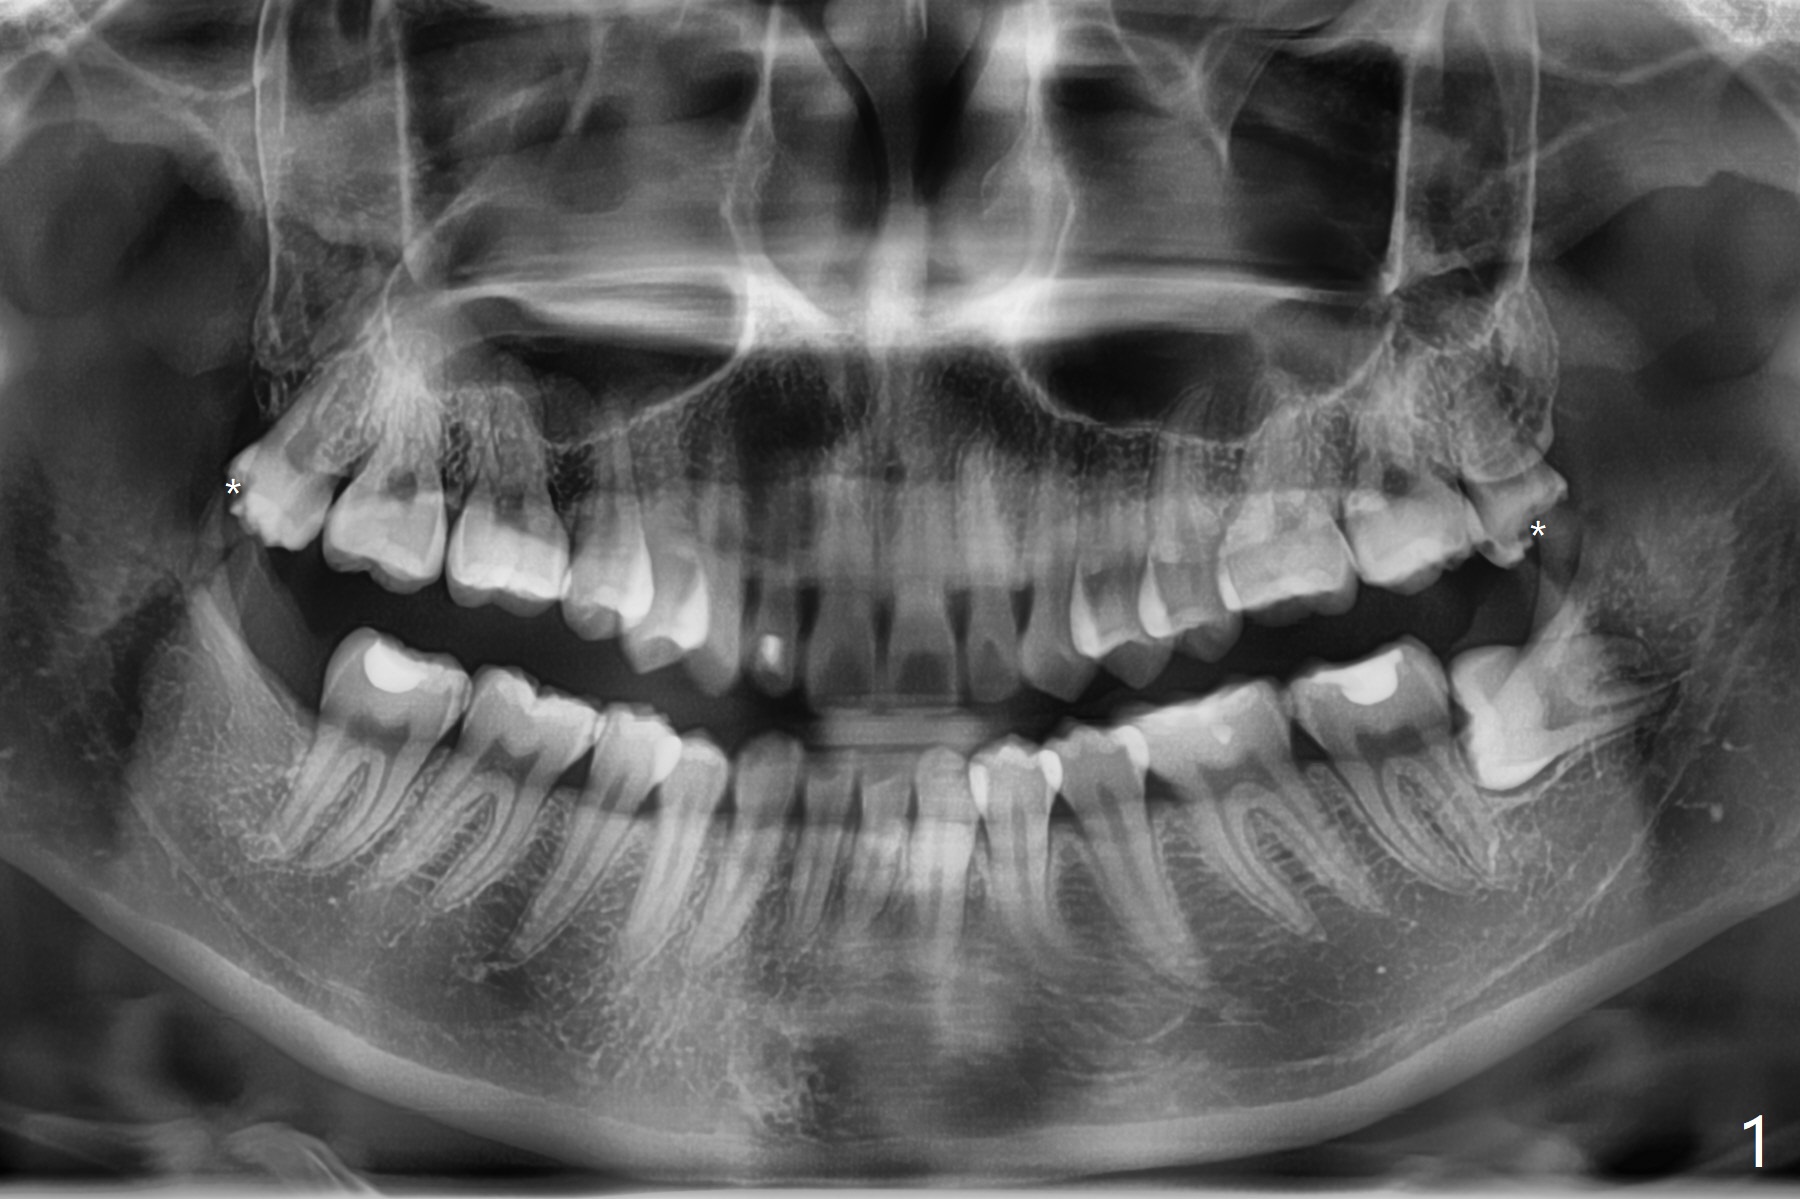

23岁女右上,左上8蛀牙(图一),左上拔除4个月后,回来拔除左下8(图二),为了防止干槽症,放置胶原塞。